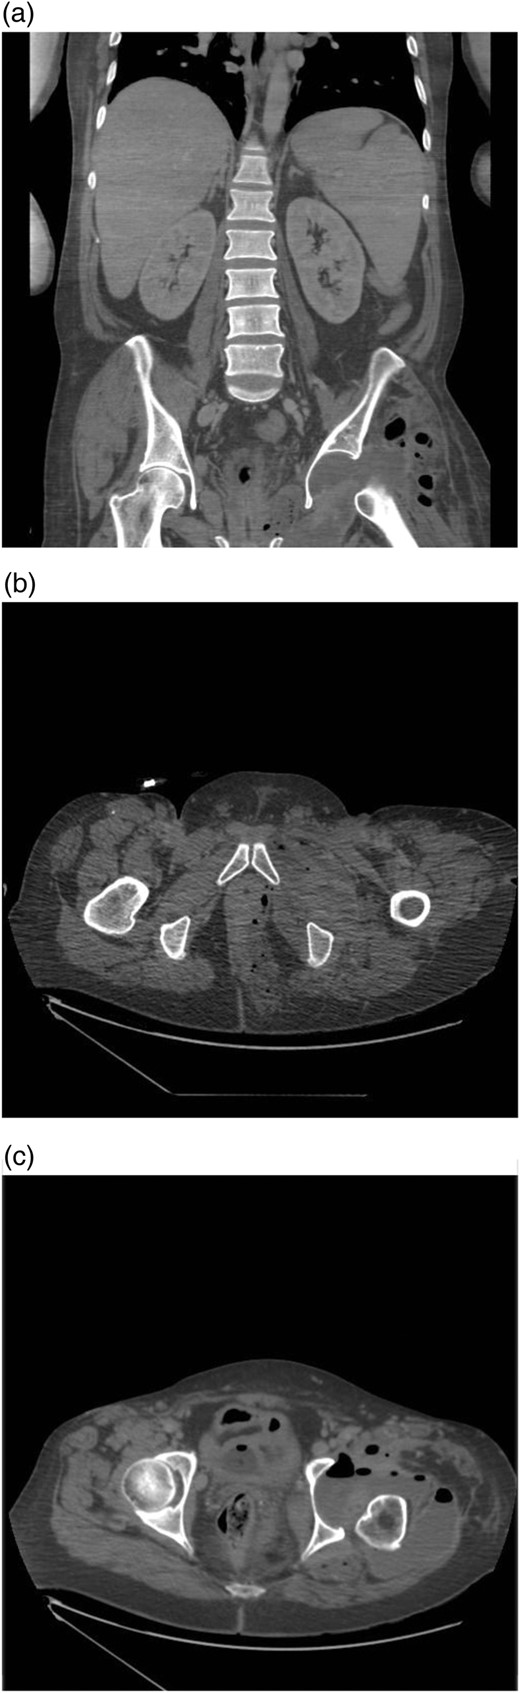

The patient's condition deteriorated and complained of increasing left sided lower abdominal and hip pain. Despite vigorous administration of intravenous fluids, serial lactate levels demonstrated a rapid increase. A computed tomography (CT) scan of the abdomen and pelvis demonstrated a moderate collection involving the musculature surrounding the left hip with gas within the soft tissue, extending to the left ischiorectal fossa and left obturator internus muscle, suggesting a communication between the bowel and hip joint. There were no features of IBD, DD or bowel carcinoma (Fig. 1).

(a) Coronal slice from a CT scan of the abdomen and pelvis showing the left hip gridlestone with the presence of air in the joint space. (b and c) Axial images demonstrating air in the lower rectum with involvement of the left ischial fossa and passage along the obturator canal to the left hip joint.